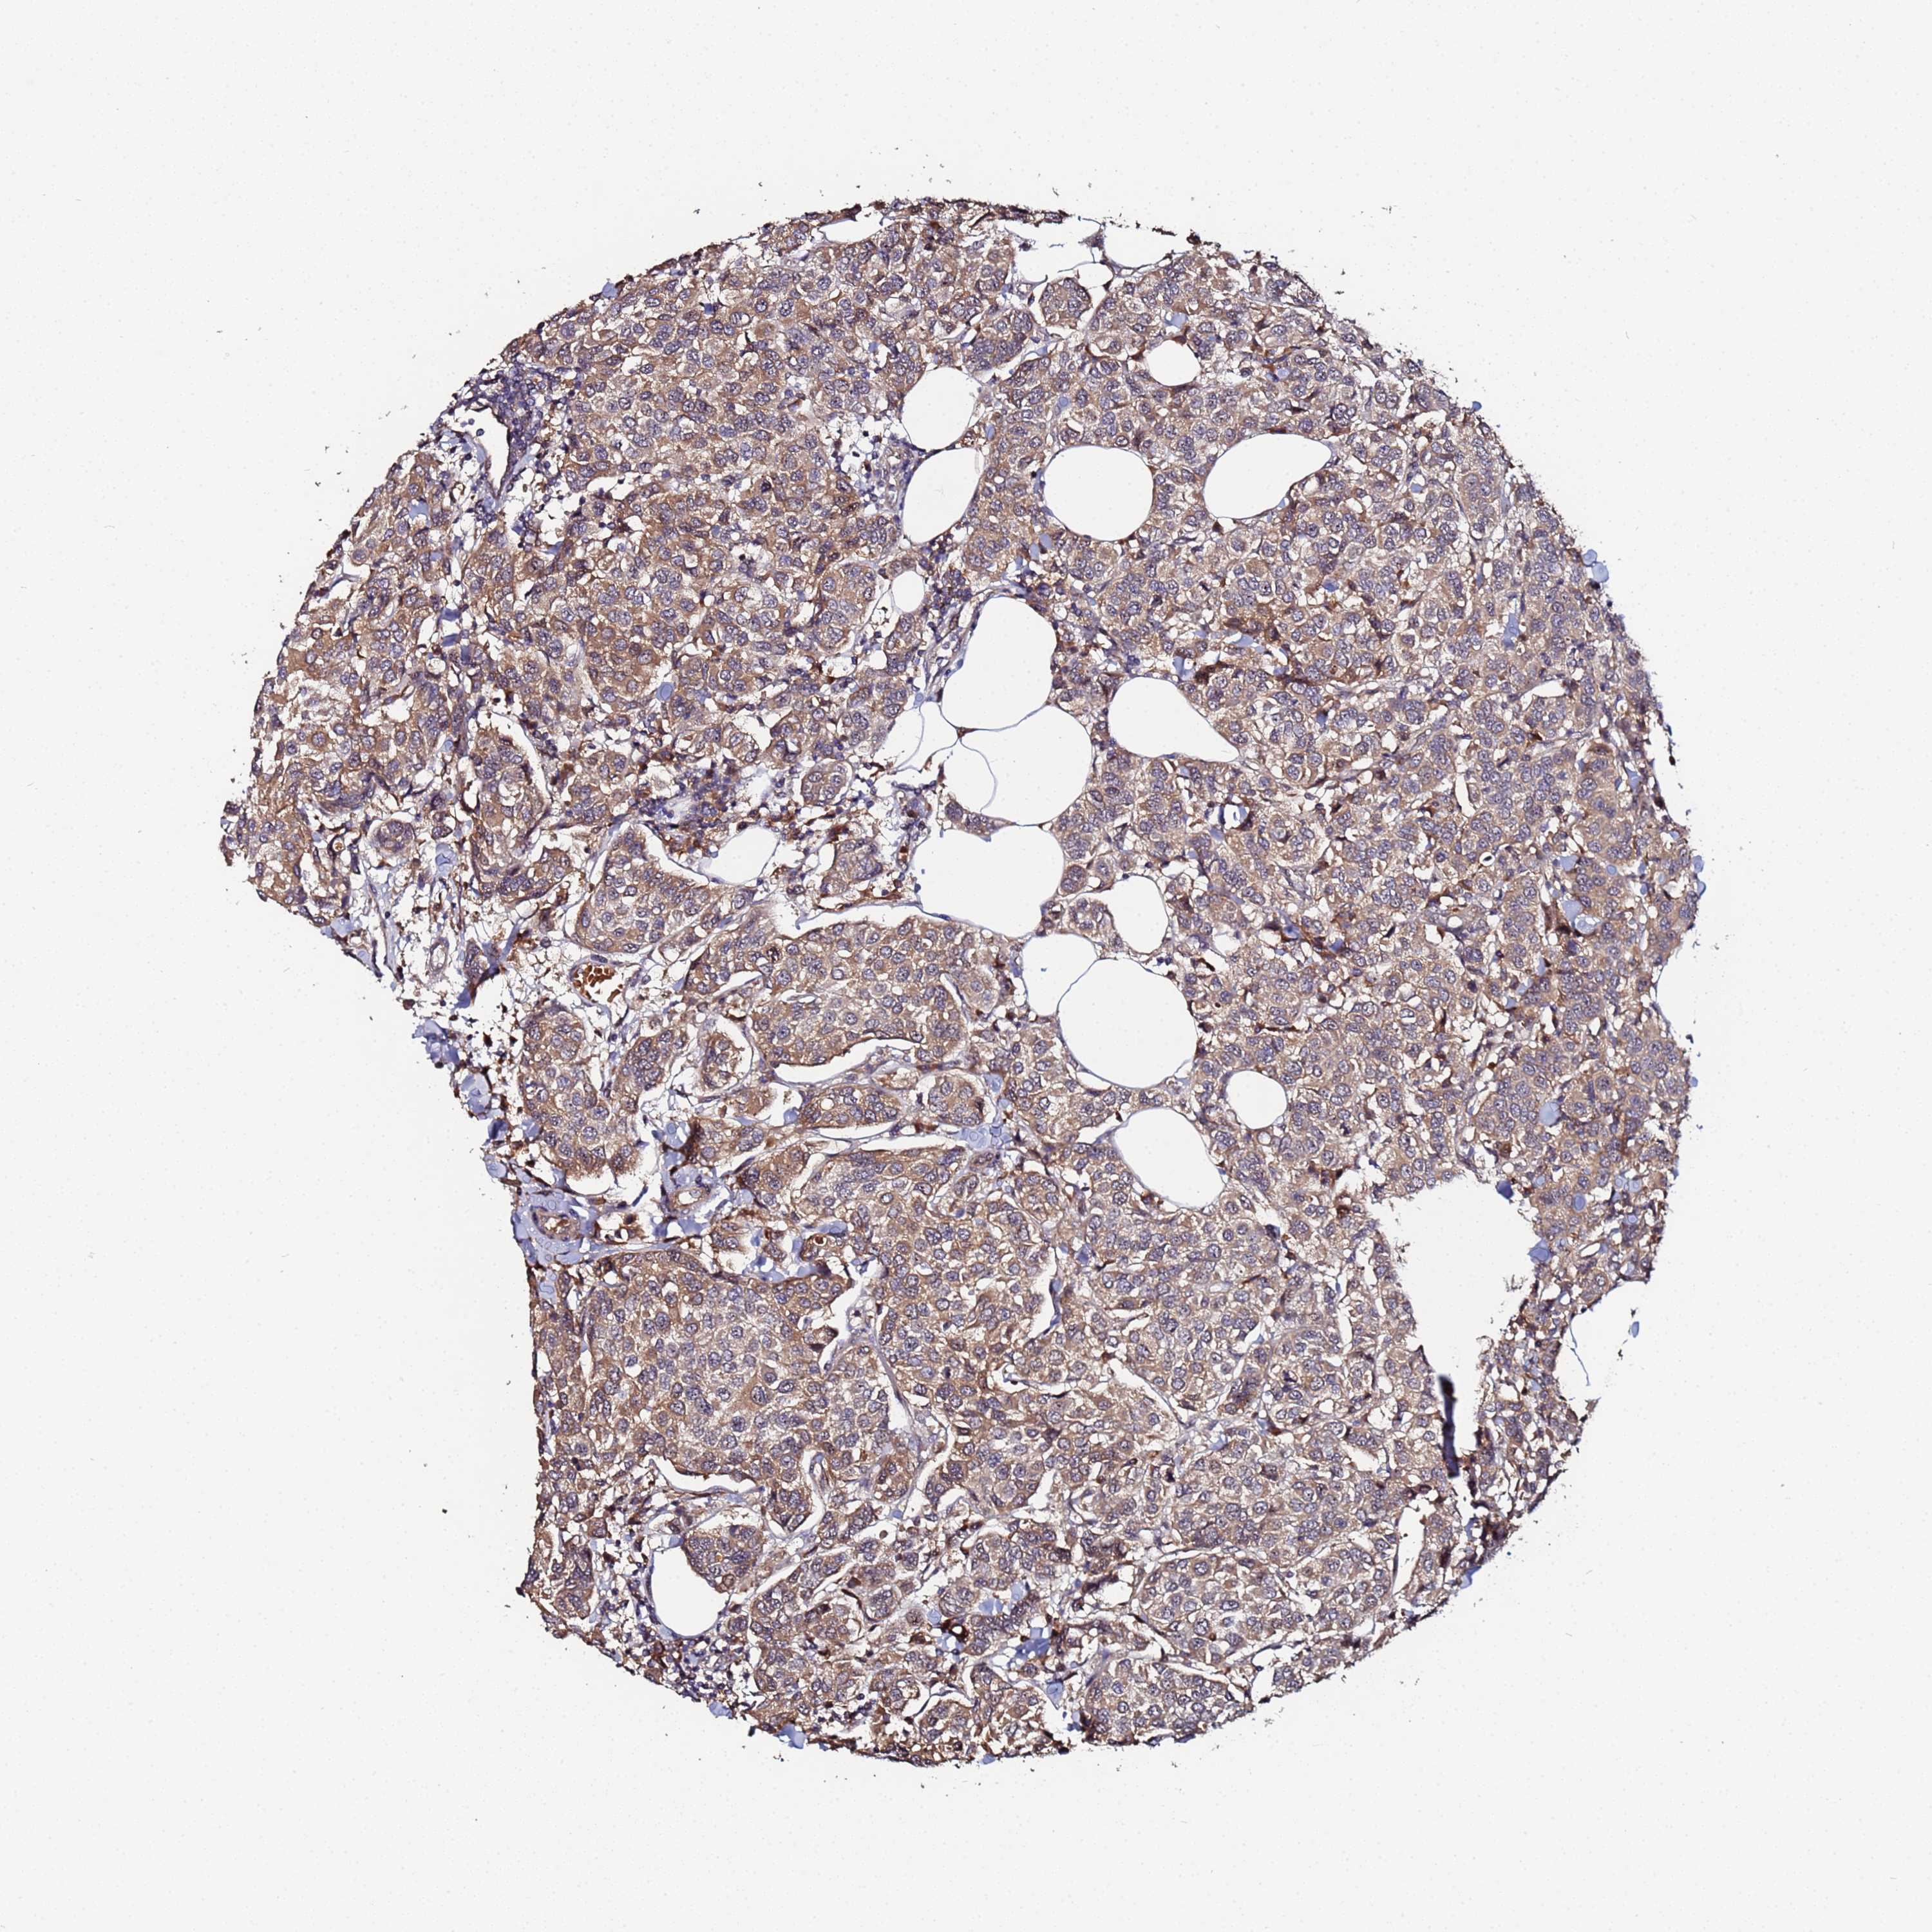

CANCER BREAST CANCER Show tissue menu

BRCA TCGA BRCA VALIDATION PROTEIN EXPRESSION